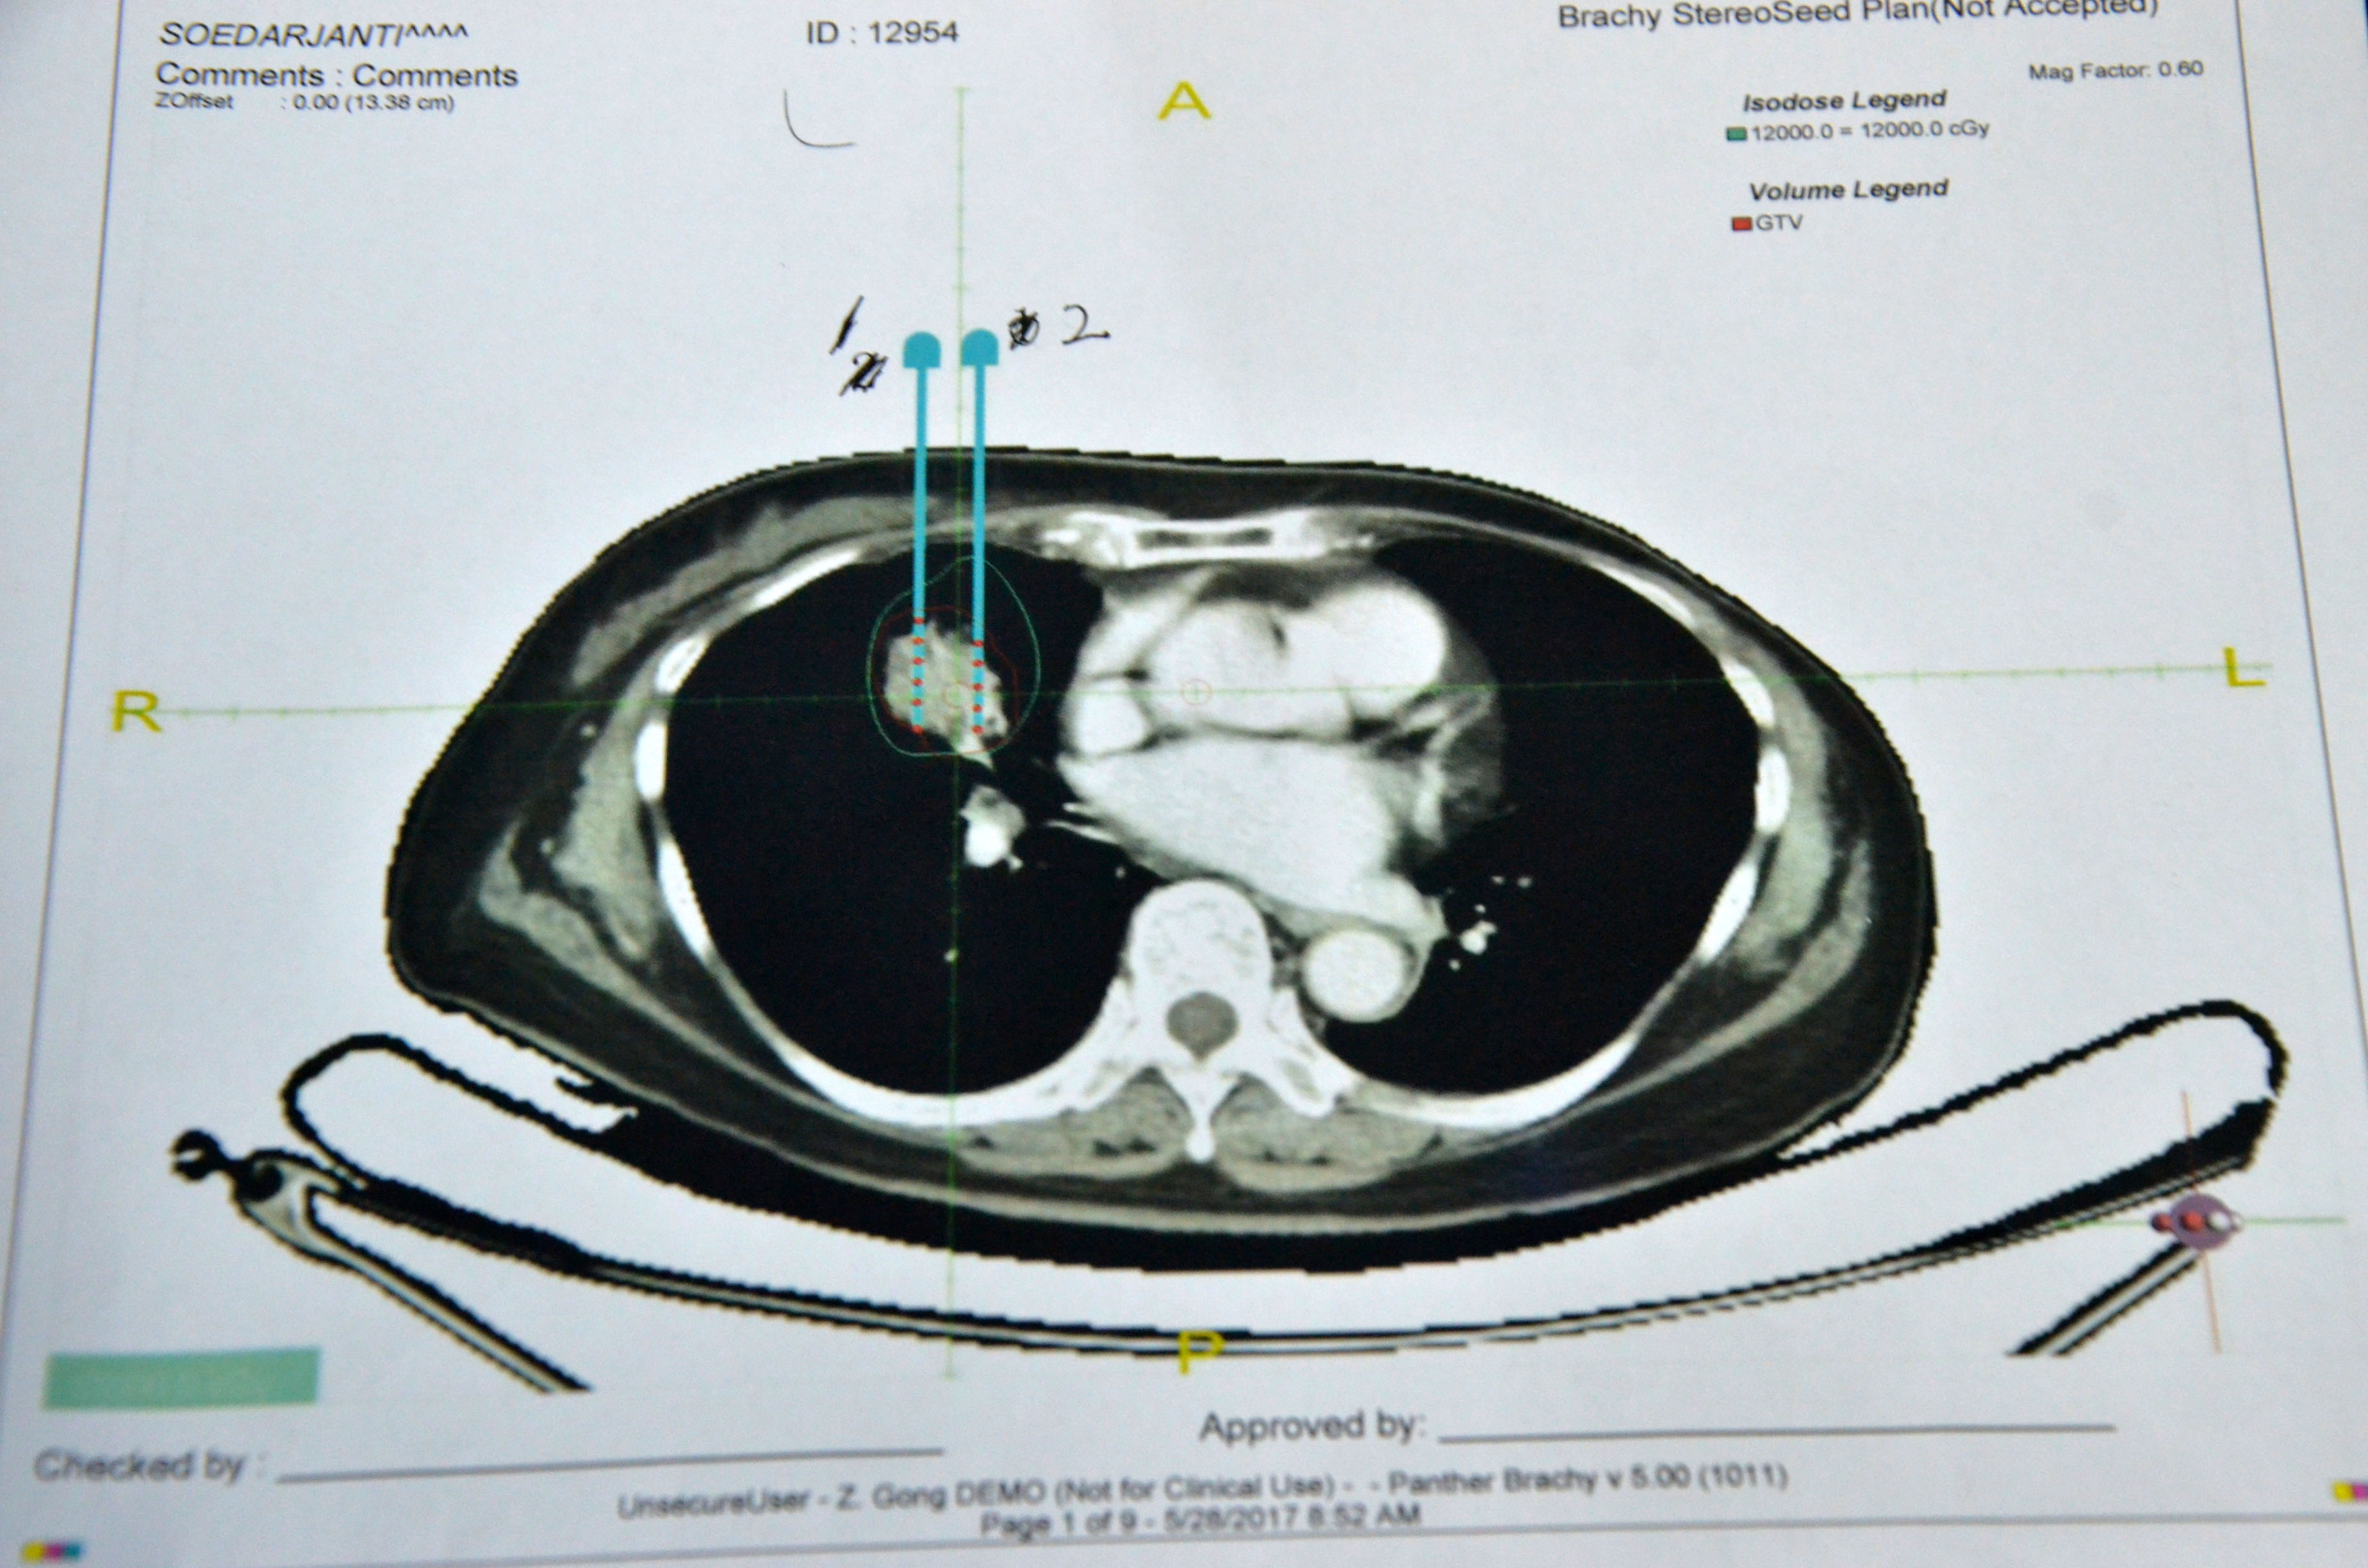

▲术前计划

患者女性,今年78岁,来自印尼,5月下旬因左下肢、右胸有明显疼痛而来到广州现代肿瘤医院。经CT检查发现,患者右肺有一个3cm大小肿瘤,伴左股骨转移,经穿刺活检确认为右肺癌Ⅳ期。经医院MDT团队讨论研究,决定为其采取3D微创导向模板引导下的I125粒子植入术。I125粒子持续低剂量组织内照射,局部肿瘤高剂量、周围正常组织低剂量,操作易行,并发症少等特点,对该患者更为适合。

术前患者进行了CT检查,利用CT进行3D建模,通过PROWESS TPS软件(粒子植入治疗计划系统)将患者肿瘤CT扫描图像进行三维重建,完整地呈现出患者皮肤、骨骼、血管和肿瘤之间的关系。设计出每一根穿刺针的进针路径、进针深度、粒子分布及粒子数量、肿瘤受辐射的剂量,最后通过3D打印设备制作出贴合患者皮肤的3D微创导向模板。